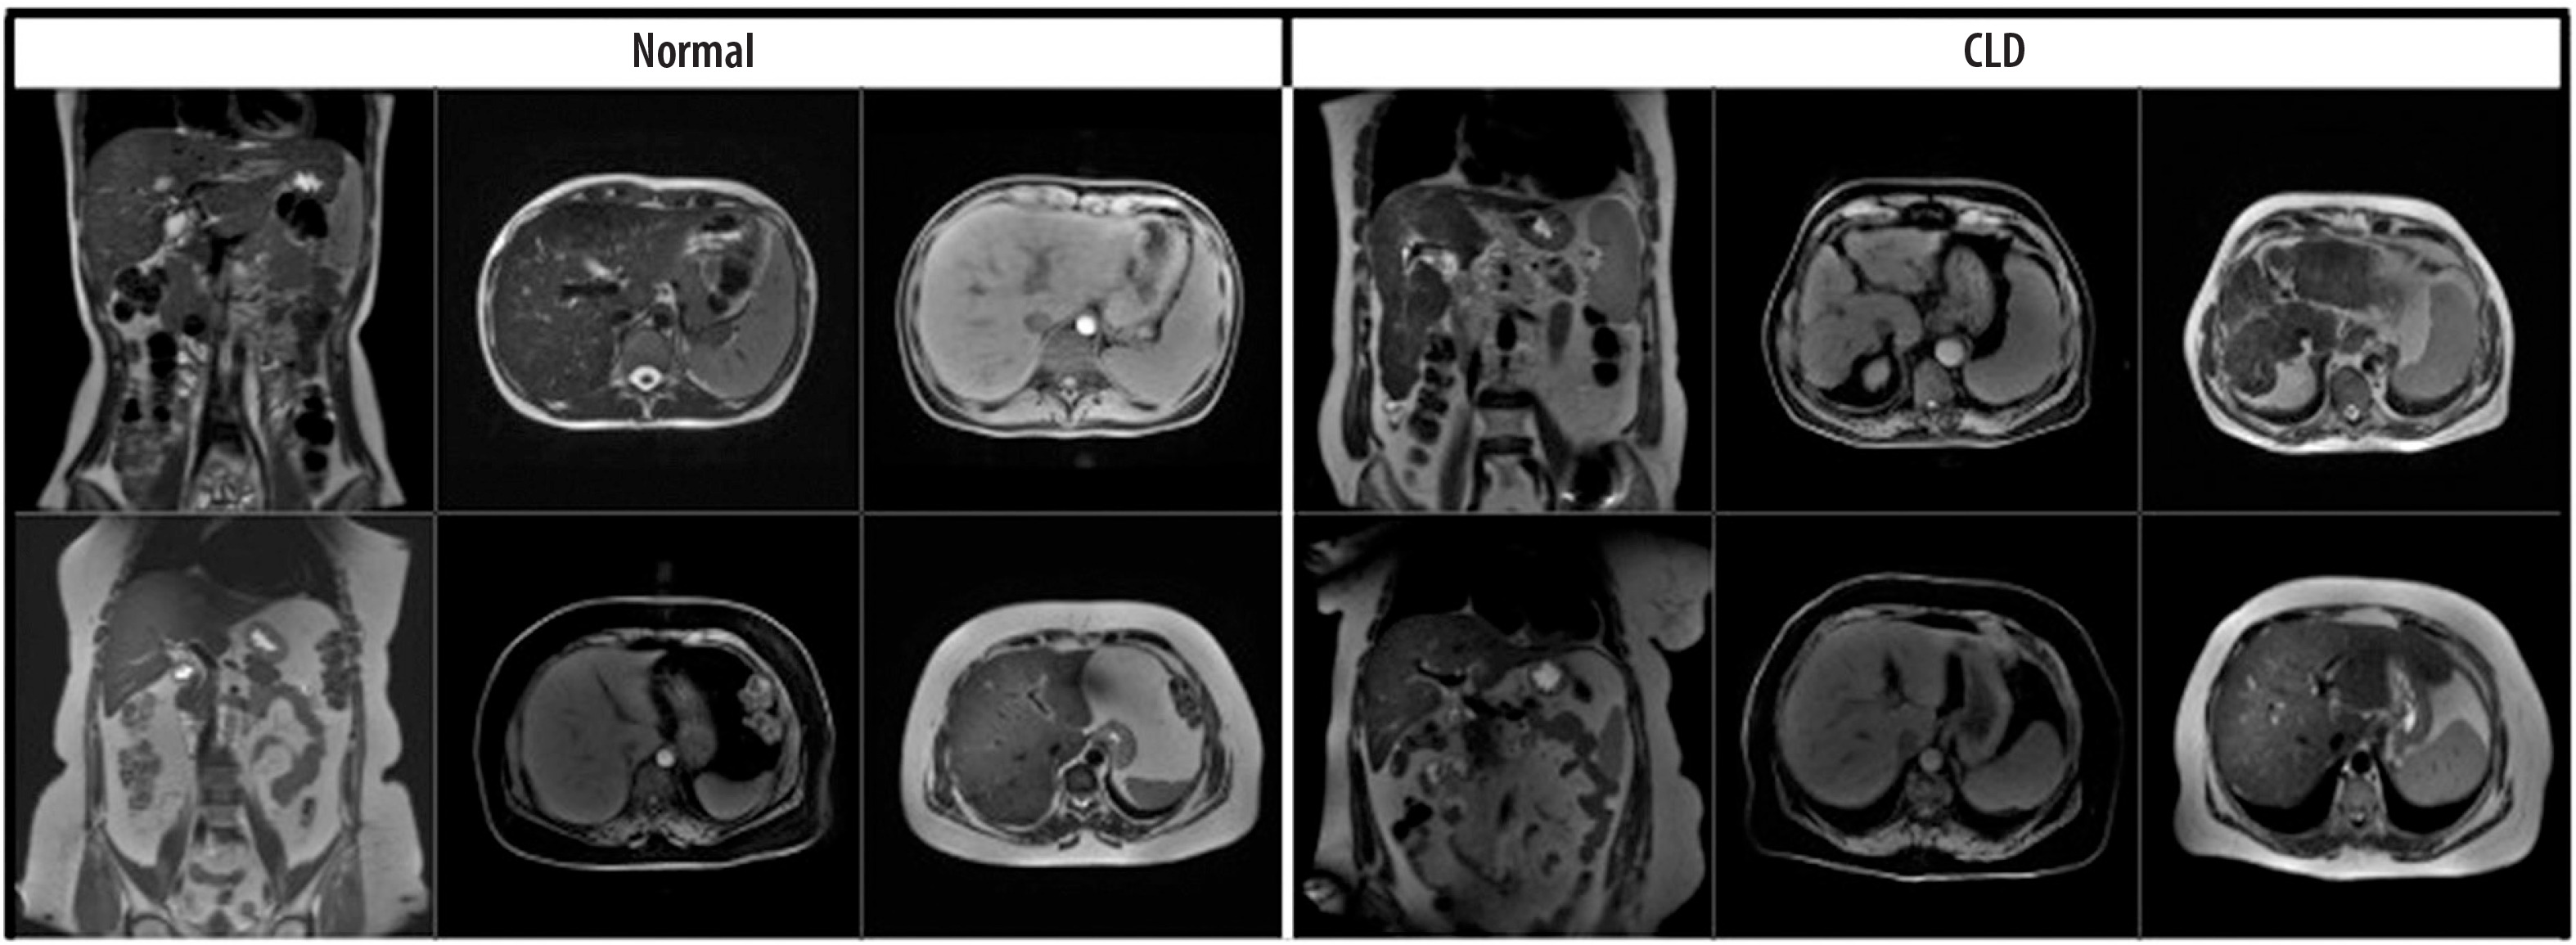

The dataset consisted of 1112 MRI slices from 184 patients, including both axial and coronal views. Specifically, 722 axial and 390 coronal images were included, and both imaging planes contained samples from normal and CLD classes. Images were input individually into the model, regardless of their orientation. No fusion method or explicit indication of image plane was used during training. This approach was chosen to evaluate the model’s ability to generalize across imaging planes and to reflect real-world variability in radiology practice. Examples of the dataset used are shown in Figure 1.

Figure 1

Coronal and axial images of normal/chronic liver disease (CLD) patients from the data set used